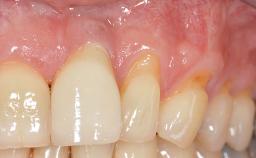

A 30-year-old woman was referred by her general dentist for evaluation of an esthetic complication related to previous implant treatment for congenitally missing maxillary lateral incisors. The patient’s chief complaint was the inadequate esthetic appearance of her smile. The case demonstrates the use of a combined approach to achieve optimal results. Two different flap designs - a tunnel technique and a coronally advanced flap - are employed based on the surgical objectives for the affected site.

Periodontal Phenotype Low-scalloped, thick Medium-scalloped, medium-thick High-scalloped, thin

Soft Tissue Anatomy Intact Defective